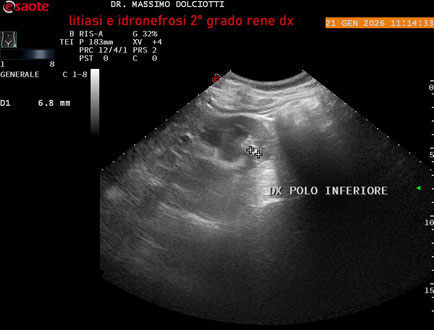

Data inserimento: 22/01/2026

Ecografia del: 21/01/2025

Strumento: Esaote MyLab Eight

Sonda: Convex Multifrequenza 1-8 MHz

Età Paziente: M 27 anni

Motivazione dell'esame: dolore al fianco destro da 3 mesi.

Commento all'esame: le immagini ed il video documentano il rene destro in sede, con ecostruttura disomogenea per evidenza, alla pelvi renale, di immagine iperecogena delle dimensioni di 16,2 mm, con cono d'ombra posteriore, da ricondurre a litiasi ed una formazione simile, di minore entità, al polo inferiore, delle dimensioni di 6,8 mm. Rene dx con diametro longitudinale di 122 mm (v.n. 90-120 mm) x 63 mm e parenchima renale dello spessore di 15 mm (v.n. > 13 mm). Rene dx con idronefrosi di 2° grado.

Conclusioni: litiasi e idronefrosi di 2° grado al rene destro (lithiasis and second-degree hydronephrosis of the right kidney).

In collaborazione: Dr.ssa Marica Manfredi - Ancona, Dr. Ilir Qose - Ancona

Presentazione: Dr. Massimo Dolciotti - Ancona

Elaborazione digitale: Andrea Dini - Ancona